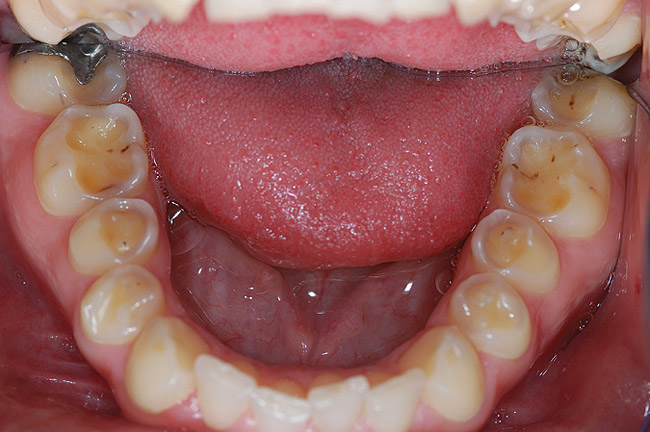

Figure 3  Left untreated and without preventive advice, erosion will continue to develop. In this case, the erosion had started to attack most tooth surfaces, making sensitivity a common finding.

Figure 3

The first signs of tooth wear may not be immediately recognizable because changes to the enamel surface can be difficult to diagnose. The mamelons on the incisal edge of incisors wear away within the first decade after eruption, but other less obvious changes also occur (Figure 1). The cusp tips of molars and premolars may flatten as may the facial surfaces of upper incisors. If allowed to progress, eventually the enamel is worn away, exposing small areas of dentin (Figure 2). Dentin exposure is much easier for dentists to recognize, but it means that considerable amounts of the tooth have been lost. Ideally, therefore, early diagnosis should help to prevent the lesion from progressing into dentin. If the process of tooth wear continues without intervention, almost total destruction of the tooth can occur (Figure 3).